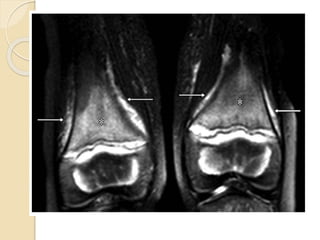

 Coronal T2-weighted fat-suppressed MR

image of both distal femoral

metadiaphyses shows heterogeneously

increased T2 signal intensity in the

marrow (*) and around the bone (arrows)

 Coronal T2-weightedfat-suppressed MR image of both distal femoral metadiaphyses shows heterogeneously increased T2 signal intensity in the marrow (*) and around the bone (arrows)